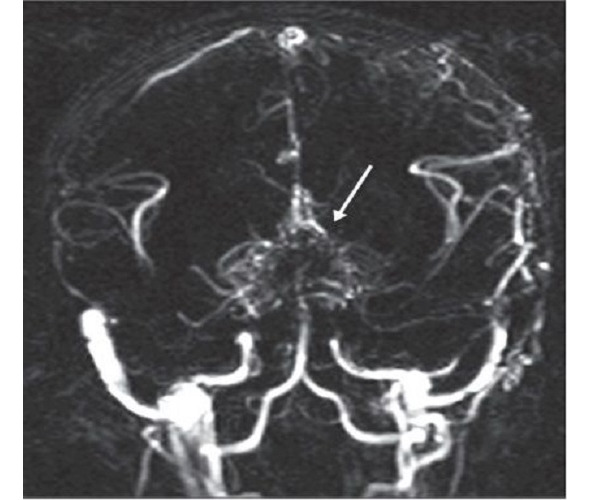

Moyamoya is a rare disease [208] characterized by a progressive spontaneous stenosis or occlusion of a supraclinoid segment of an ICA (single or both) at the level of the siphon and the initial segments of the anterior cerebral artery (ACA) and the middle cerebral artery (MCA) with the subsequent involvement of the VBS. The specific feature of this disease is the secondary formation of a basilar, anastomotic capillary network, resembling a small cloud of smoke (Fig. 4) during the angiographic imaging, which is pronounced in Japanese as «moyamoya». This word has become an official name of the disease. In 40% of cases in the moyamoya disease a bilateral impairment of the ICA is noted; initially the ICA is involved only on one side [233; 285]. The «moyamoya syndrome» term is more often used for angiographic description of the pathology [266].

Fig. 4: MRA of a patient with the moyamoya disease. The secondary formation of anastomotic network resembling a cloud of smoke is indicated with an arrow.